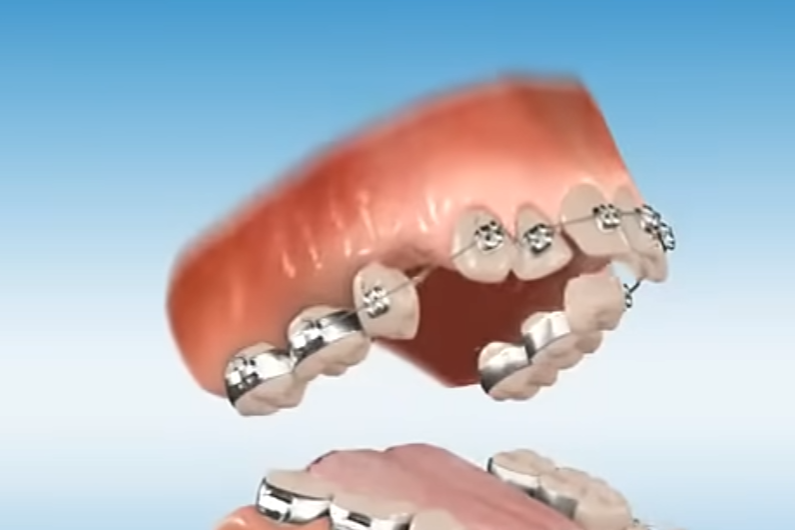

basically if orthodont only removes your UPPER 4th 2 molars will it still recess you? (in overbite case) because i heard people completely have their bone structure fallen because of upper and lower jaw molar extractions. i dont need extractions from both, just 2 4th molars from upper jaw. thanks